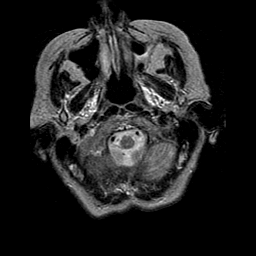

Pick's Disease, MR Study mr-t2 -- Slice #1

[Home][Help][Clinical] Slice 1